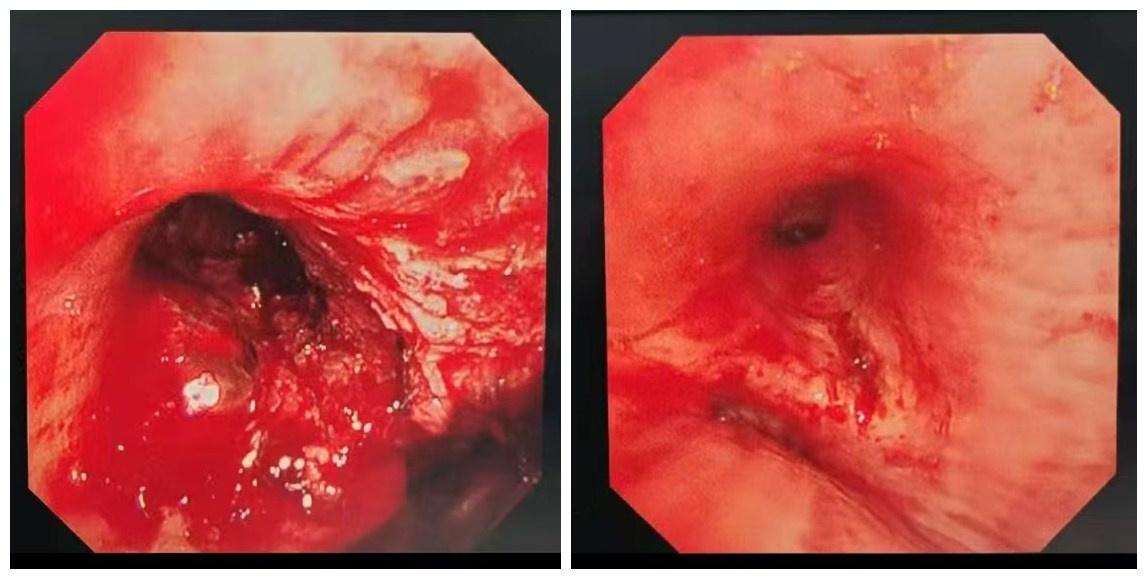

手术由费建文指导,呼吸与危重症医学科、支气管镜室、手术室、麻醉科等多学科医护人员共同配合,呼吸介入团队数秒内插入硬质气管镜,应用圈套器、电刀、氩气刀、冷冻术等操作技术去除大量肿瘤组织及坏死物。

术中取出的肿瘤组织及坏死物。